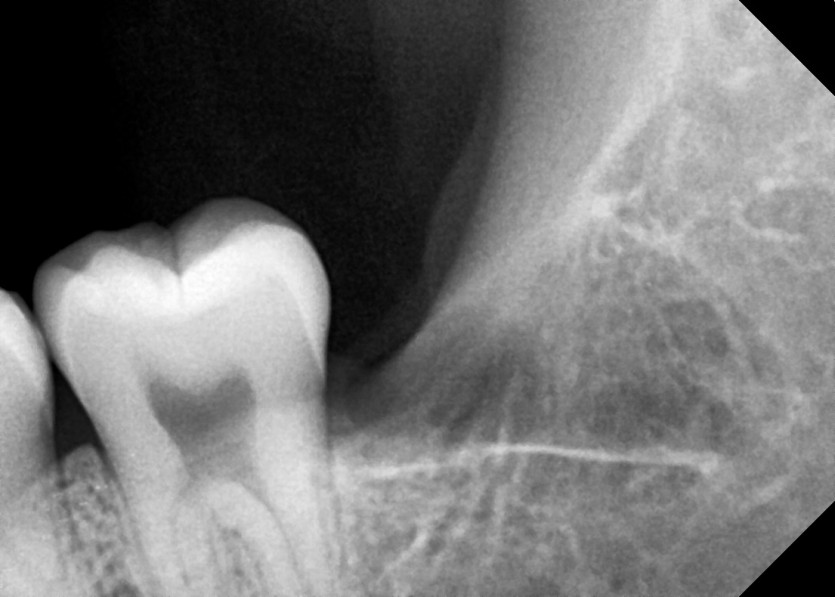

#18,28,38,48 사랑니 발치

구강 외과 전문의가 당일 발치했습니다.